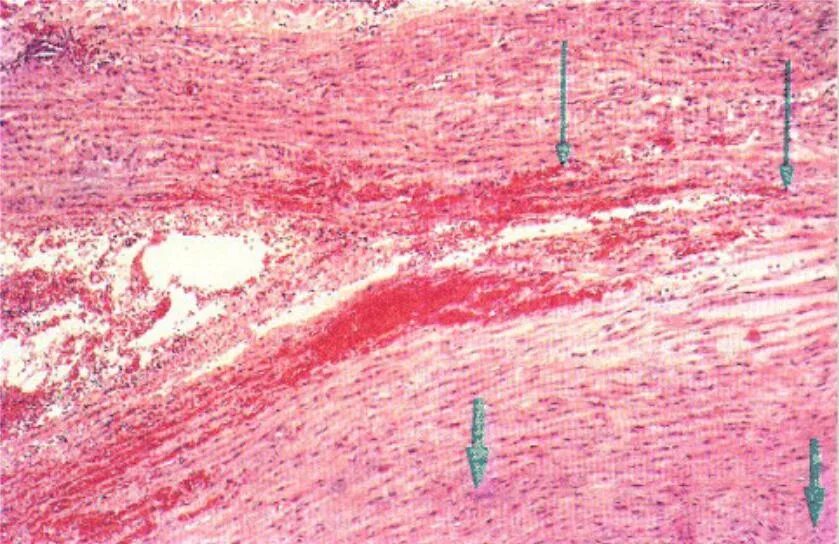

Атеросклероз аорты препарат